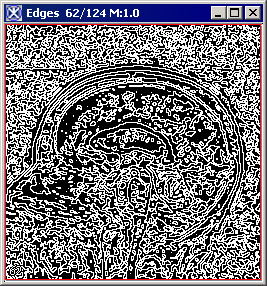

The algorithm begins to run, and a status window appears. When the algorithm finishes, the resulting image appears as an unsigned byte mask in a new image window as shown in Figure 3.

Figure 3. The original image and its unsigned byte mask with detected edges